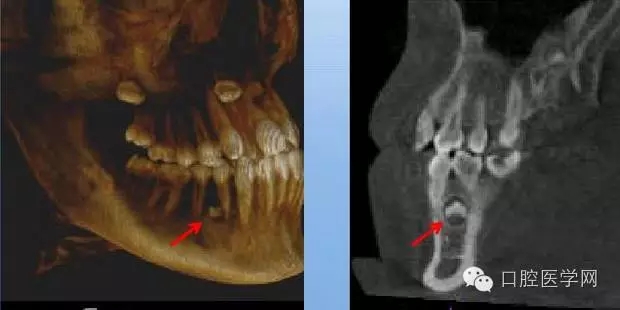

牙根異常(數(shù)目異常、形態(tài)異常)

X線表現(xiàn):恒磨牙及上頜雙尖牙多見,注意頰舌側(cè)根重疊雙層牙周膜影響,確定牙根變異的類型和程度。